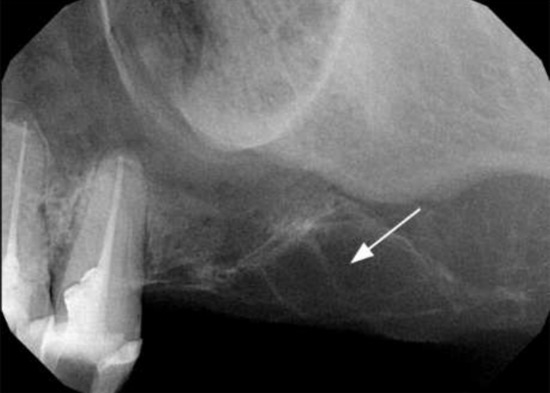

1.1. Case Report